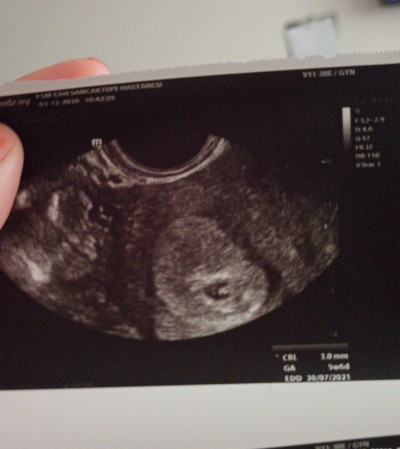

Merhaba bugün 7.haftama girdim beta değerlerim normalin altında ilerliyor bebeğim normal ultrsonda gözükmedi vajinal yoldan bakıldığında dün kalp atışını duyduk dedi doktorlar normalde gozukmeden bebek nasıl kalp atışlarını duydular anlayamadım hastanede yattım 1 gece kan değerlerimi takip ettiler sürekli  bebeğim vajinal yoldan görüldü ama sağlıksız gebelik dediler öyle oluncada 12. Haftaya kadar düşme ihtimali çok yüksek mis ilk gebeliğim ve çok korkuyorum bu durumda olan varmi cevap verirmisiniz lütfen.

Gebelik haftası 7